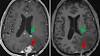

Living drugs that reprogram patients' immune cells show early promise against hard-to-treat brain tumors From left, brain tumors, marked by red and green arrows, disappear a day after CAR-T immunotherapy treatment. From Penn Medicine.

A new strategy to attack aggressive brain cancer shrank tumors in two early tests Researchers revved up immune cells that shrank an extremely aggressive type of brain tumor when tested in a handful of patients. ByLAURAN NEERGAARD AP medical writer. March 13, 2024, 2:03 PM.

Massachusetts clinical trial shows 'dramatic and rapid' progress against glioblastoma tumors A new treatment for a lethal brain cancer known as glioblastoma has shown remarkable early results, new research from the Mass General Cancer Center shows. The New England Journal of Medicine published results of a phase 1 clinical trial of a novel ...